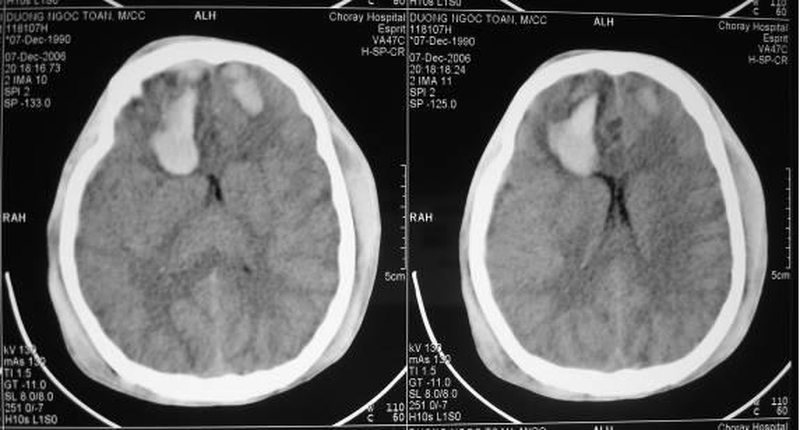

Chụp cắt lớp vi tính (CT):

Xét nghiệm này thường được thực hiện trong phòng cấp cứu nếu người bệnh bị nghi ngờ là chấn thương sọ não. Chụp CT có thể giúp bác sĩ nhận biết các xương bị gãy và phát hiện các tình trạng:

• Xuất huyết hoặc chảy máu bên trong tế bào não

• Tụ máu, có khối máu đông

• Mô não bị bầm tím, nhiễm trùng

• Sưng mô não

cac-hinh-anh-chan-thuong-so-nao-1Phương pháp chụp cắt lớp vi tính (CT) để xét nghiệm hình ảnh chấn thương sọ não